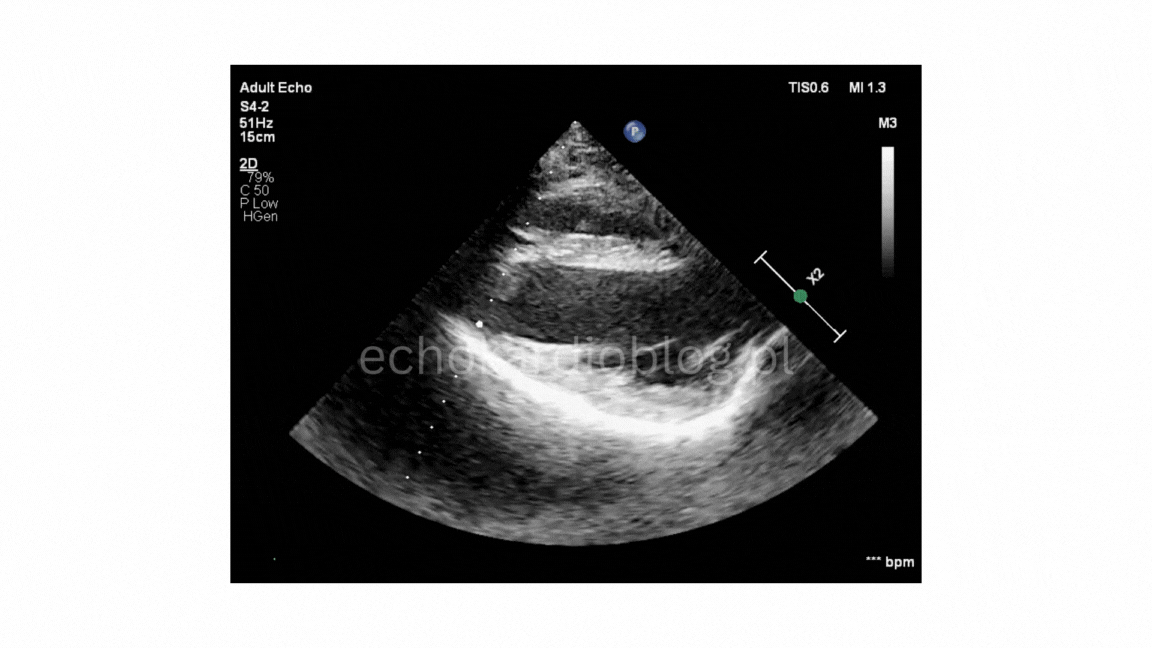

Podsumowanie: Deformacja mostka może zaburzać geometrię prawej komory i ruch przegrody

międzykomorowej, naśladując patologię serca. Echo pozwala to precyzyjnie odróżnić – warto o tym

pamiętać u pacjentów z lejkowatą klatka piersiową.

Summary:

Sternal deformity may significantly disturb the geometry of the right ventricular and septal motion,

mimicking true cardiac pathology. Echocardiography helps distinguish these mechanical effects – an

important point to remember in patients with pectus excavatum.